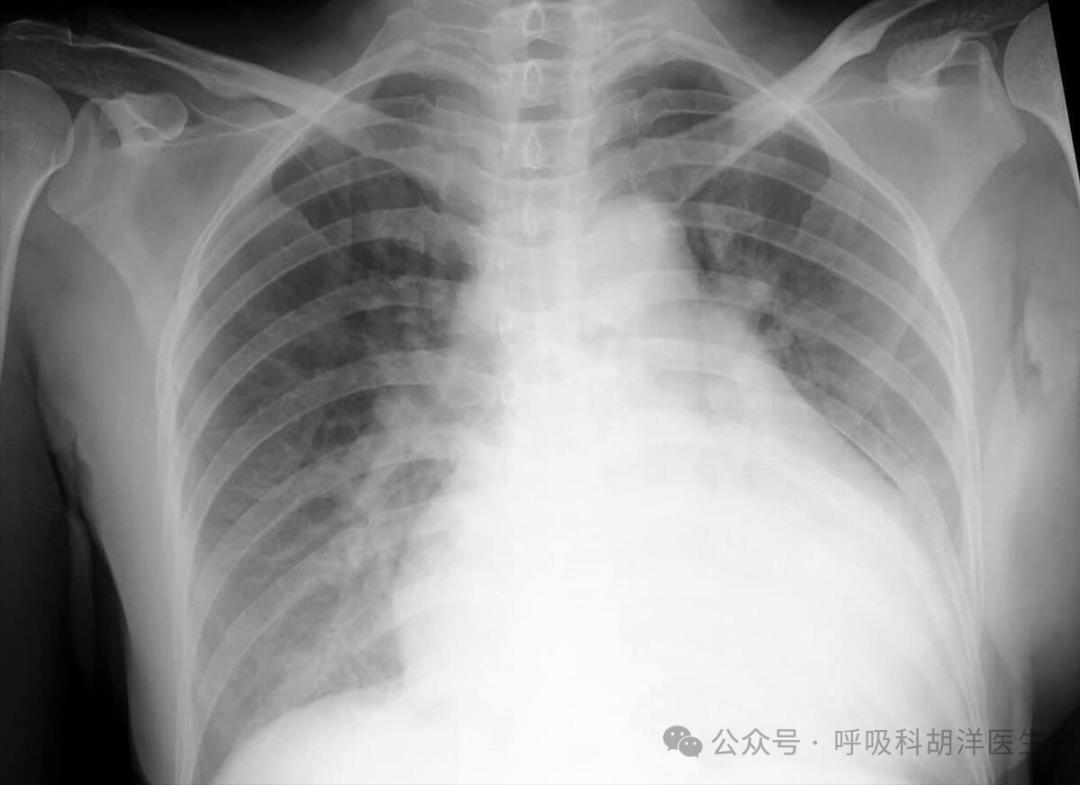

患者肺部弥漫式磨玻璃阴影,心跳快,下肢水肿,心力衰竭指标达到2000多。人们感到不舒服,感到无法呼吸。住院后,他紧急治疗心力衰竭。疾病很快好转,心力衰竭指标改善了很多,脚也不肿了。复查肺部影像,磨玻璃阴影也消散出院。

综上所述,如果肺部出现磨玻璃阴影,不一定是肺部原发性疾病,也可能是心脏问题影响肺部。